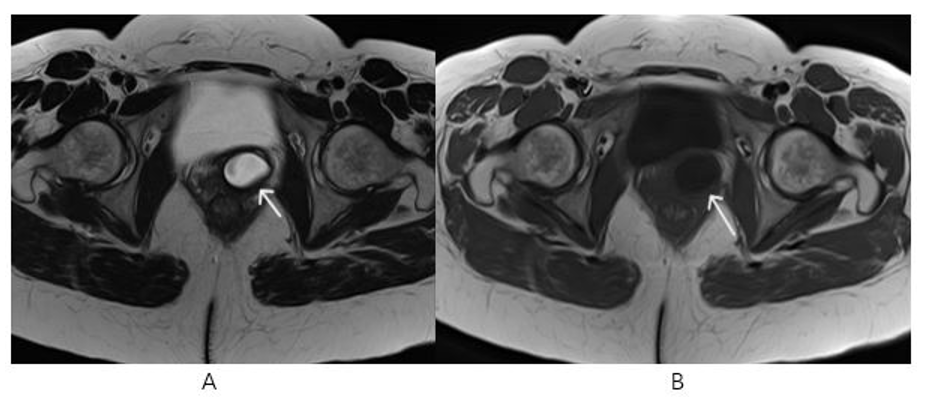

On non-enhanced MRI was detected a cyst with regular contours at the left anterolateral wall of the proximal 1/3 part of the vagina(Figure 1, Figure 2, Figure 3

Figure 1, 2: Pelvic MR Non-Enhanced Axial T2 (A) and Axial T1 (B) Images ( White Arrows): Cystic Structure with Regular Contours at the Left Anterolateral Wall of the Proximal 1/3 Part of the Vagina.